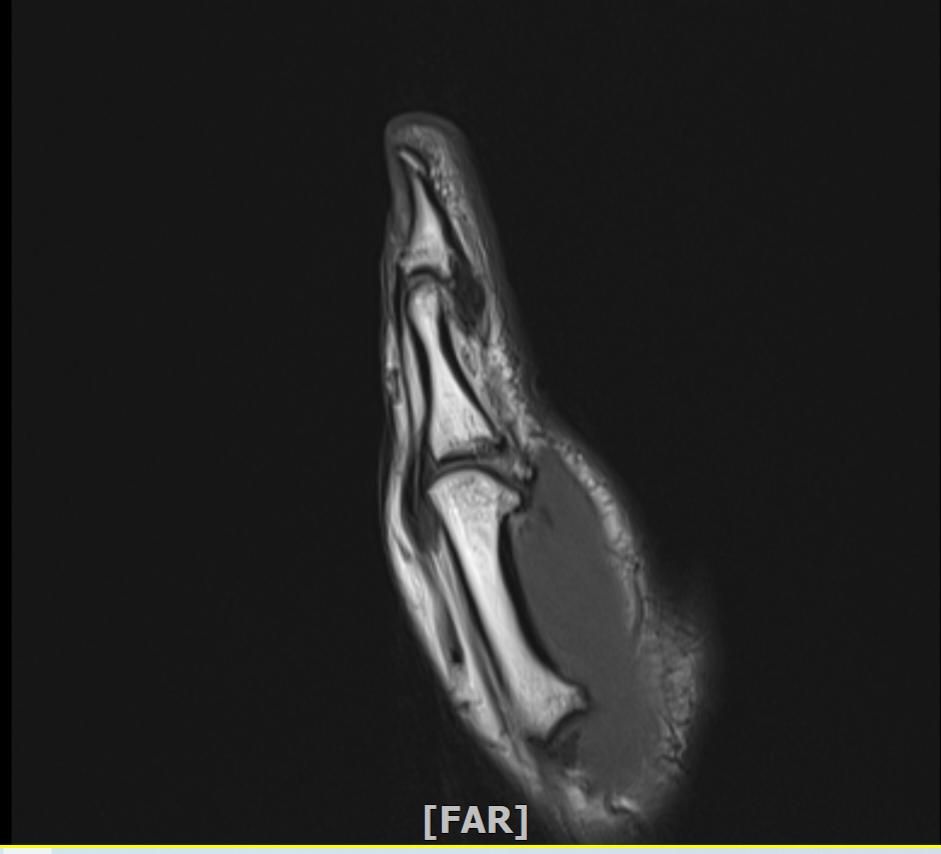

mri 엄지손가락 미세골절 여부확인

공구에 왼손이 말려서 엄지를 다쳤습니다 응급실에서 부목고정 조치후 이틀후 mri촬영 하였습니다.

엄지손가락 뼈가 자주 욱씬거리는데 미세골절 여부 확인 부탁드립니다.

• 2번 째 사진

우선 현재로썬 MRI 사진으론 정확한 판단을 하긴 어렵지만 주변 연부조직의 손상이 보여집니다.

다만 미세골절 같은 경우는 여러 방면의 판독이 필요하므로 정확한 판독은 병원에 내원하셔서 MRI 촬영을 한 병원에 판독지를 받으시고 전문의에 판독을 받으시길 적극 추천드립니다.